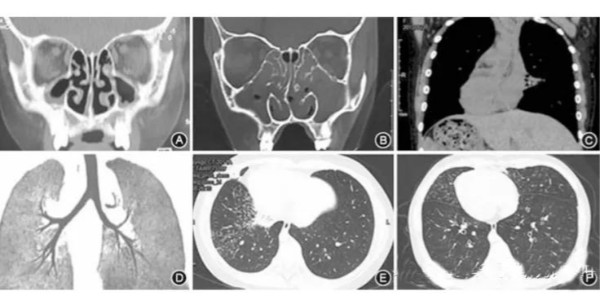

图 7 患儿影像学检查结果。A:鼻窦CT示双侧上颌窦炎(男,11岁);B:鼻窦CT示双侧上颌窦炎和鼻中隔偏曲(女,11岁);C:CT冠状位成像可见左肺局部肺不张、右位心和腹腔脏器反位(女,11岁);D:CT气道重建可见气管左右结构反位(女,10月龄);E:右肺CT可见较多小叶中心型微结节(女11岁);F:双肺CT可见支气管扩张和细支气管炎(男,11岁). (引自靳雨婷等,中华儿科杂志, 2015